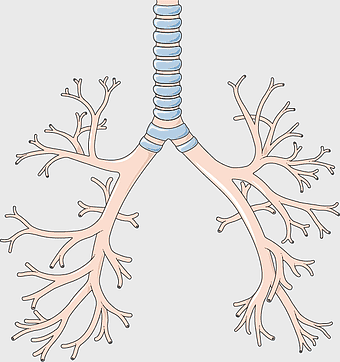

Bronchus anatomy, respiratory system illustration, pulmonary alveoli structure, creative lung art, human respiratory health, medical respiratory diagram, tree-like lung branches -